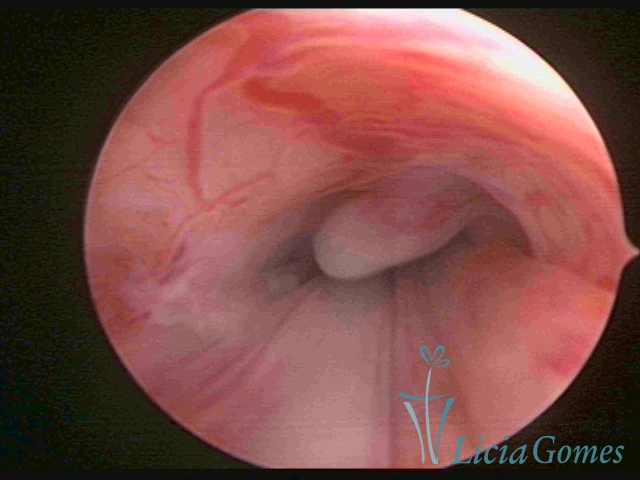

ENDOCERVICAL POLYPS

Benign tumors resulting from the reactive focal proliferation to inflammatory processes or hyperestrogenism situations, which may be sessile (with a large implantation) or stalked.